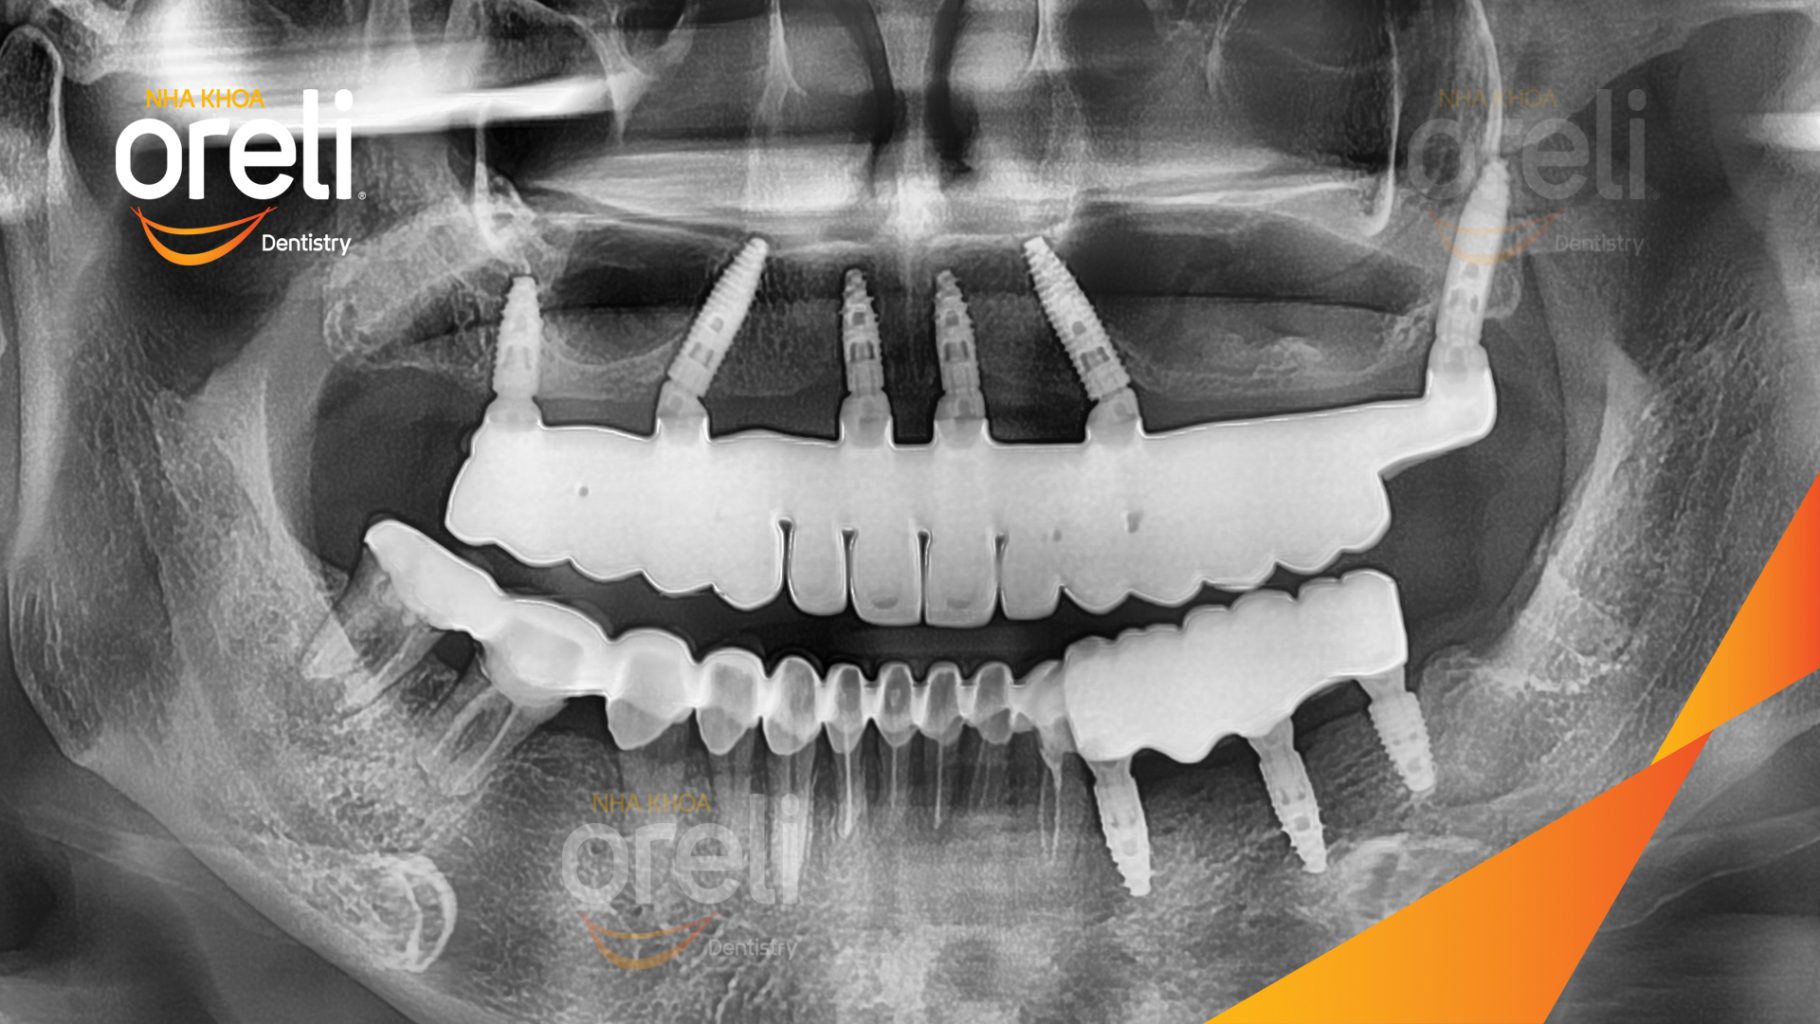

Ca trồng răng implant hàm trên và ba răng hàm dưới hình ảnh trước sau

Ca trồng răng implant toàn hàm phục hồi ăn nhai và thẩm mỹ nụ cười. Kết quả thực tế trước và sau điều trị tại Nha khoa Oreli.

Giải pháp: Cắt bỏ cầu răng nhổ các chân răng trồng implant all on six

Kết quả: Thẩm mỹ tự nhiên ăn nhai chắc chắn

Hình ảnh thực tế